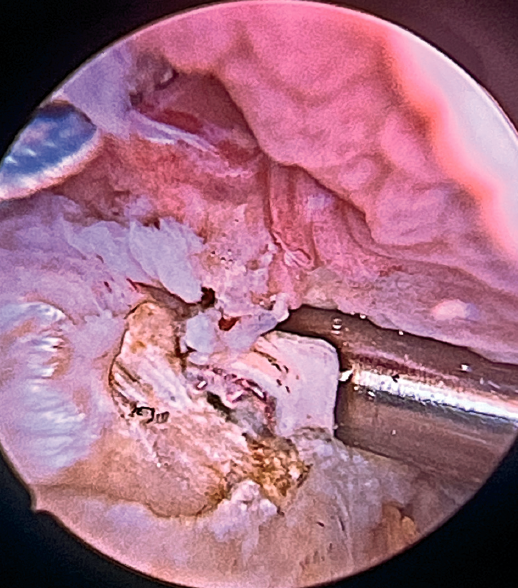

Preparation of the bone footprint and autologous graft of the long portion of the biceps

The greater tuberosity is then prepared with the bone drill, creating a bleeding bone surface to enhance tendon-bone healing, as this is where both cuff repair and augmentation with biceps will be carried out (Figure 1).